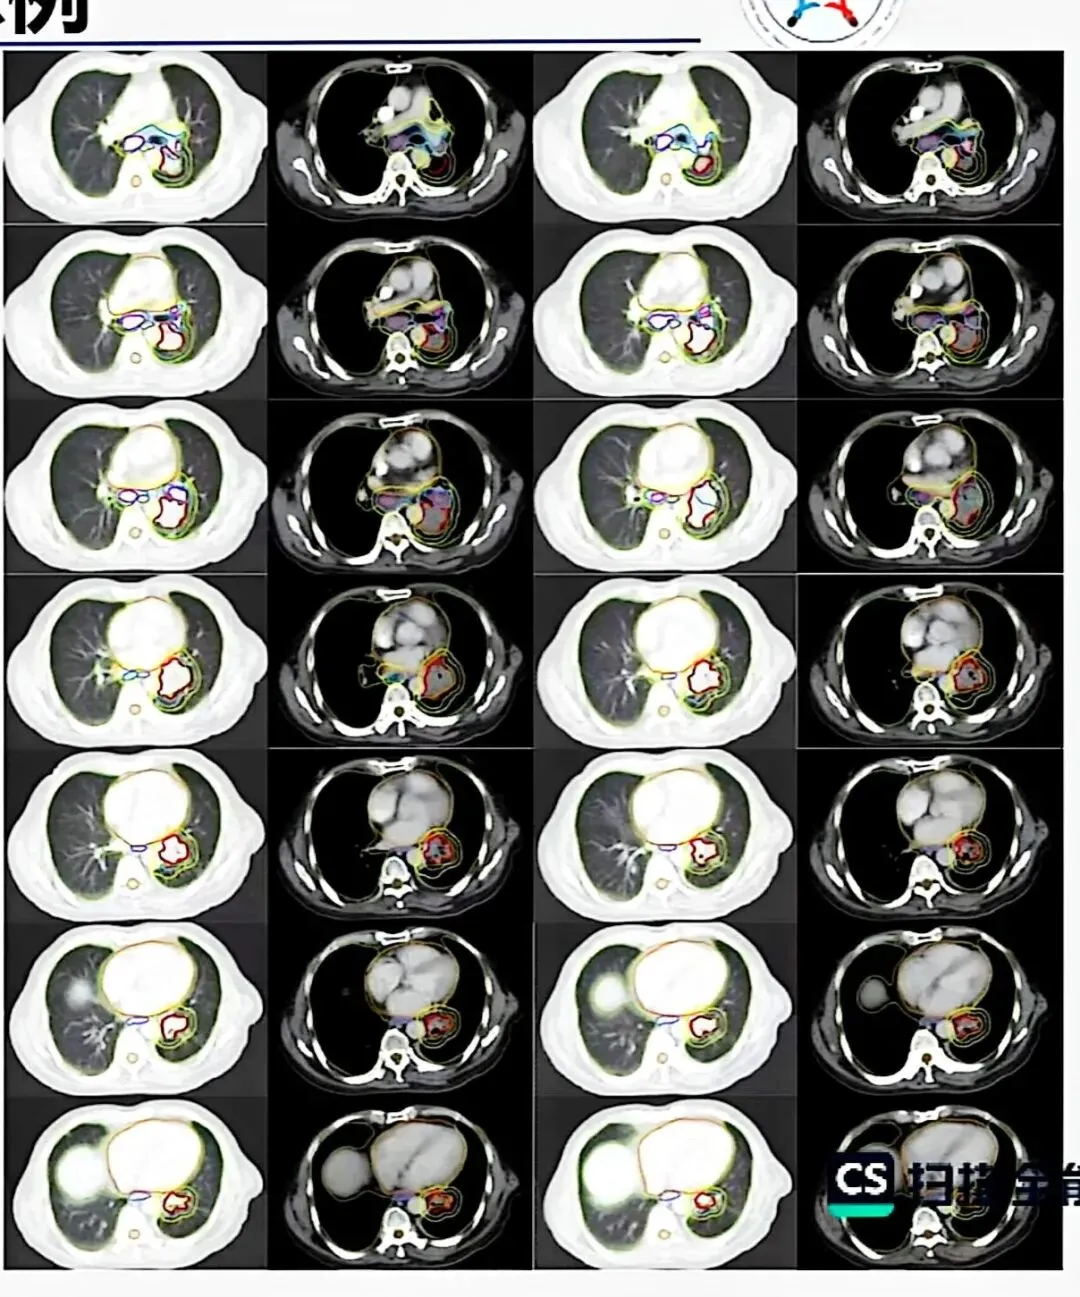

四、靶区勾画:从理论到实践

1. ICRU靶区定义体系

GTV(肿瘤靶区) :影像学可见的肿瘤原发灶和转移淋巴结。

GTV-T(原发灶)在肺窗勾画;

GTV-N(淋巴结)在纵隔窗勾画。

CTV(临床靶区) :GTV加亚临床病灶范围。

腺癌外扩8mm,鳞癌外扩6mm,外扩后需根据解剖屏障手工修剪。

ITV(内靶区) :CTV加呼吸运动范围。

PTV(计划靶区) :ITV加摆位误差,一般外扩5mm。

2. 现代靶区勾画理念:从ENI到IFRT

传统预防性淋巴结照射(ENI) 范围大,毒性高。

现代理念转向累及野照射(IFRT),仅照射影像学可见的肿瘤及受累淋巴结区域。

支持证据:研究表明,IFRT与ENI的淋巴结失败率无显著差异,但毒性显著降低。

在保证肿瘤控制的前提下,通过缩小照射体积降低毒性,提高治疗比。

1.NSCLC靶区勾画要点

原发灶:肺窗勾画,毛刺处理需个体化(短毛刺全包,长毛刺包根部)

淋巴结:短轴≥1cm或PET阳性需包含在GTV-N内

新辅助化疗后:原发灶按化疗后范围勾画,淋巴结按化疗前受累范围勾画